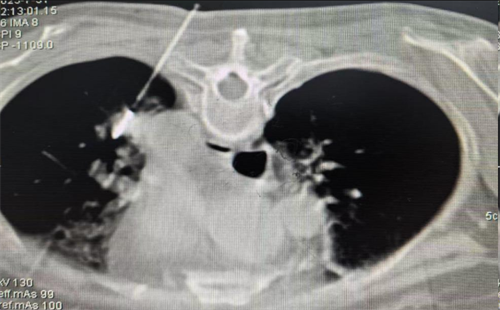

术中精准定位肺转移瘤位置